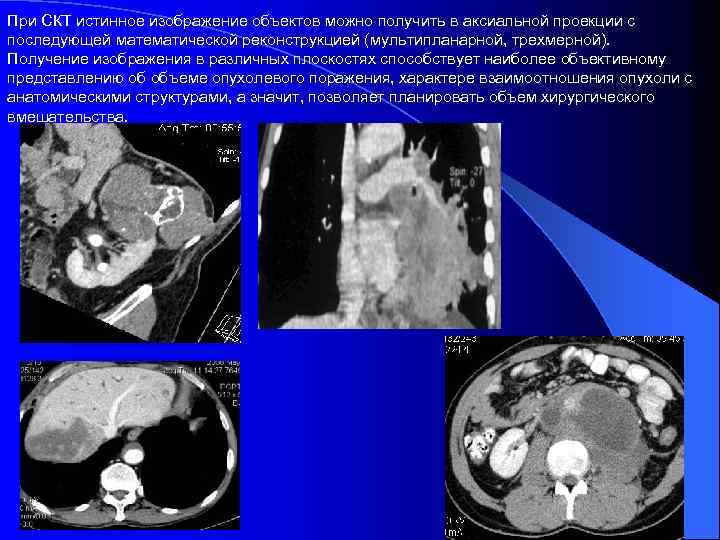

При СКТ истинное изображение объектов можно получить в аксиальной проекции с последующей математической реконструкцией (мультипланарной, трехмерной). Получение изображения в различных плоскостях способствует наиболее объективному представлению об объеме опухолевого поражения, характере взаимоотношения опухоли с анатомическими структурами, а значит, позволяет планировать объем хирургического вмешательства.